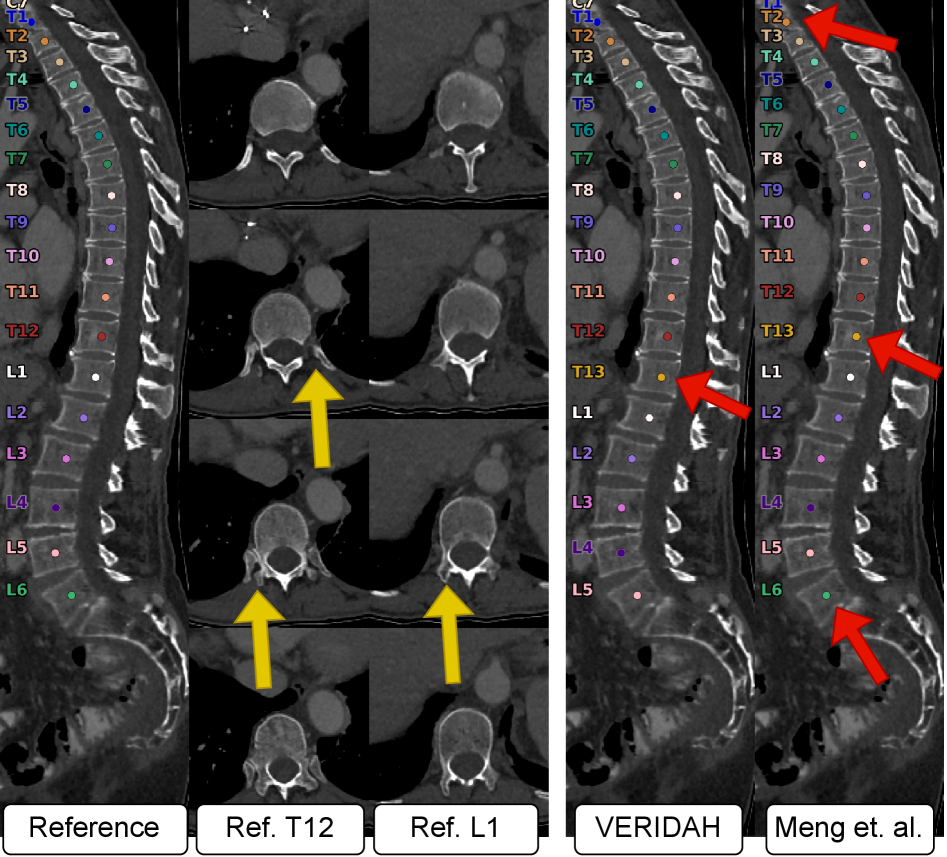

4.1 CT

VERIDAH achieves significantly better metric values than Meng et al. (see Table 3, all ). While Meng et al. provide decent results for LEA recall, they fail to correctly annotate TEA cases, regardless of whether we set their anomaly penalty cost to zero. Notably, VERIDAH achieves better performance on non-anomalous cases, as indicated by the superior subject correctness with much higher mean and lower standard deviation. When we set the punishment cost for TEA to zero, their perfect label percentage drops slightly while the TEA recall significantly increases. However, with compared to VERIDAH’s , this is still inferior. For a qualitative example, see Figure 4. Notably, on our test set, in contrast to Meng et al., the predicted labels of VERIDAH were never shifted by more than one (see Figure 5 for example).